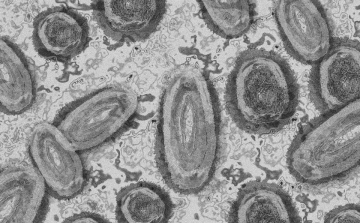

Meghaladta a 13 ezret a majomhimlő-fertőzöttek száma az Egyesült Államokban

Meghaladta a 13 ezret a majomhimlő-fertőzöttek száma az Egyesült Államokban, a legtöbb esetet Kaliforniában és New York államban regisztrálták.